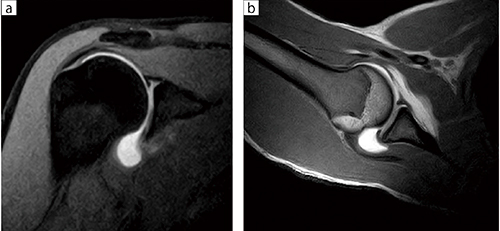

■症例2:MR Arthrography(APERTO Eterna)

肩関節腔内にGd造影剤,ウログラフイン,生食,カルボカインを透視下にて注射し,T2強調画像,脂肪抑制T1強調画像(a),ABER位T1強調画像(b)にて関節唇の剥離を評価する。

オープンMRIはABER位がとりやすく,磁場中心で撮像が可能で肩関節の機能撮像に適している。

a:T1WI,FatSat,COR,FOV:200,TR/TE:731/15,スライス厚:4mm

b:T1WI,ABER位,FOV:200,TR/TE:580/13,スライス厚:4mm